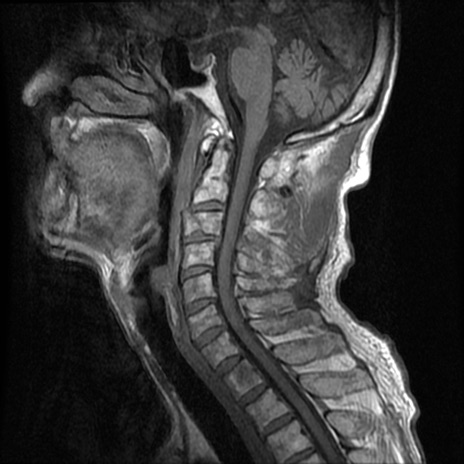

頚椎MRI

T1WI(横断像)

T2*WI(横断像)

T2WI(矢状断像)